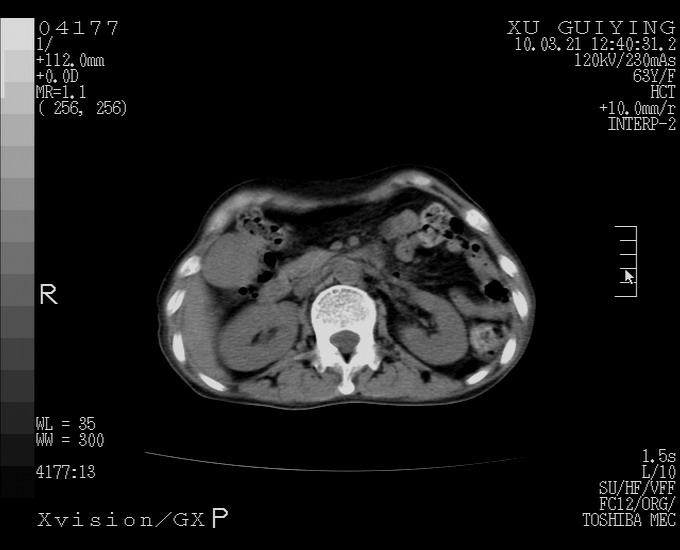

怎么没有增强呢?胆囊那么大,密度有些高啊。

慢性胆囊炎,胆囊占位不排除,建议增强或彩超。

考虑胆囊炎 不除外泥沙样结石

胆囊体积增大,胃窦壁增厚

胆囊体积增大,密度不均匀,结石不除外;胃壁增厚,考虑胃癌,建议增强。

胆囊体积增大,密度增高,较均匀,外缘也较光滑,应考虑胆囊炎。因为胃未充盈,不好说壁增厚。肝左叶及脾门处见低密度灶,有可能是血管瘤,不排除囊肿。建议超声检查或强化。